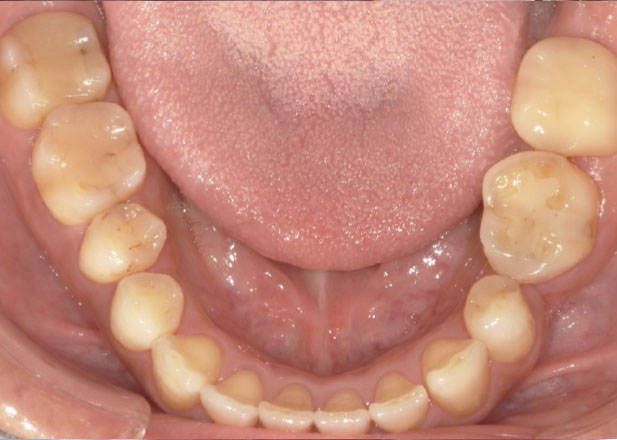

治療後

マウスピース矯正 マウスピース矯正 マウスピース矯正